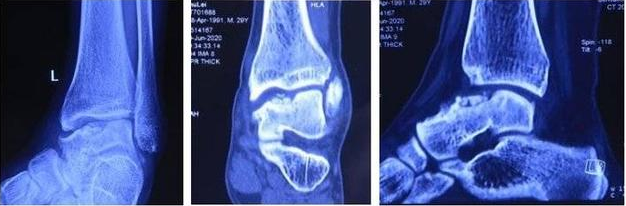

患者,男,28歲,左踝關(guān)節(jié)疼痛1年,加重3個(gè)月,影像學(xué)表現(xiàn)為左距骨內(nèi)髁壞死、塌陷,面積約3*2cm大小。距骨壞死的治療,對(duì)直徑在2cm以內(nèi)的距骨壞死,可以采用自體股骨髁骨軟骨移植、自體帶骨膜髂骨移植等方法,但對(duì)于直徑超過2cm的距骨壞死,尤其是年輕患者,一直是治療的難點(diǎn)。搜索國(guó)內(nèi)外文獻(xiàn),對(duì)于超過2cm距骨壞死,一般采用踝關(guān)節(jié)融合、踝關(guān)節(jié)置換、同種異體距骨移植、全距骨置換等方法。但上述方法均有弊端:采用關(guān)節(jié)融合,患者喪失踝關(guān)節(jié)功能;踝關(guān)節(jié)置換、全距骨置換對(duì)于年輕、距骨單髁壞死患者,創(chuàng)傷大,且需要多次的返修手術(shù);國(guó)外有采用同種異體新鮮距骨移植的報(bào)道,但目前國(guó)內(nèi)還沒有相關(guān)的骨組織工程庫(kù)。經(jīng)手術(shù)團(tuán)隊(duì)術(shù)前充分討論,認(rèn)為3D打印技術(shù)因其個(gè)性化的設(shè)計(jì)已經(jīng)越來越多地應(yīng)用于臨床,決定對(duì)患者行3D打印距骨部分置換手術(shù)。

△術(shù)前3D打印設(shè)計(jì)